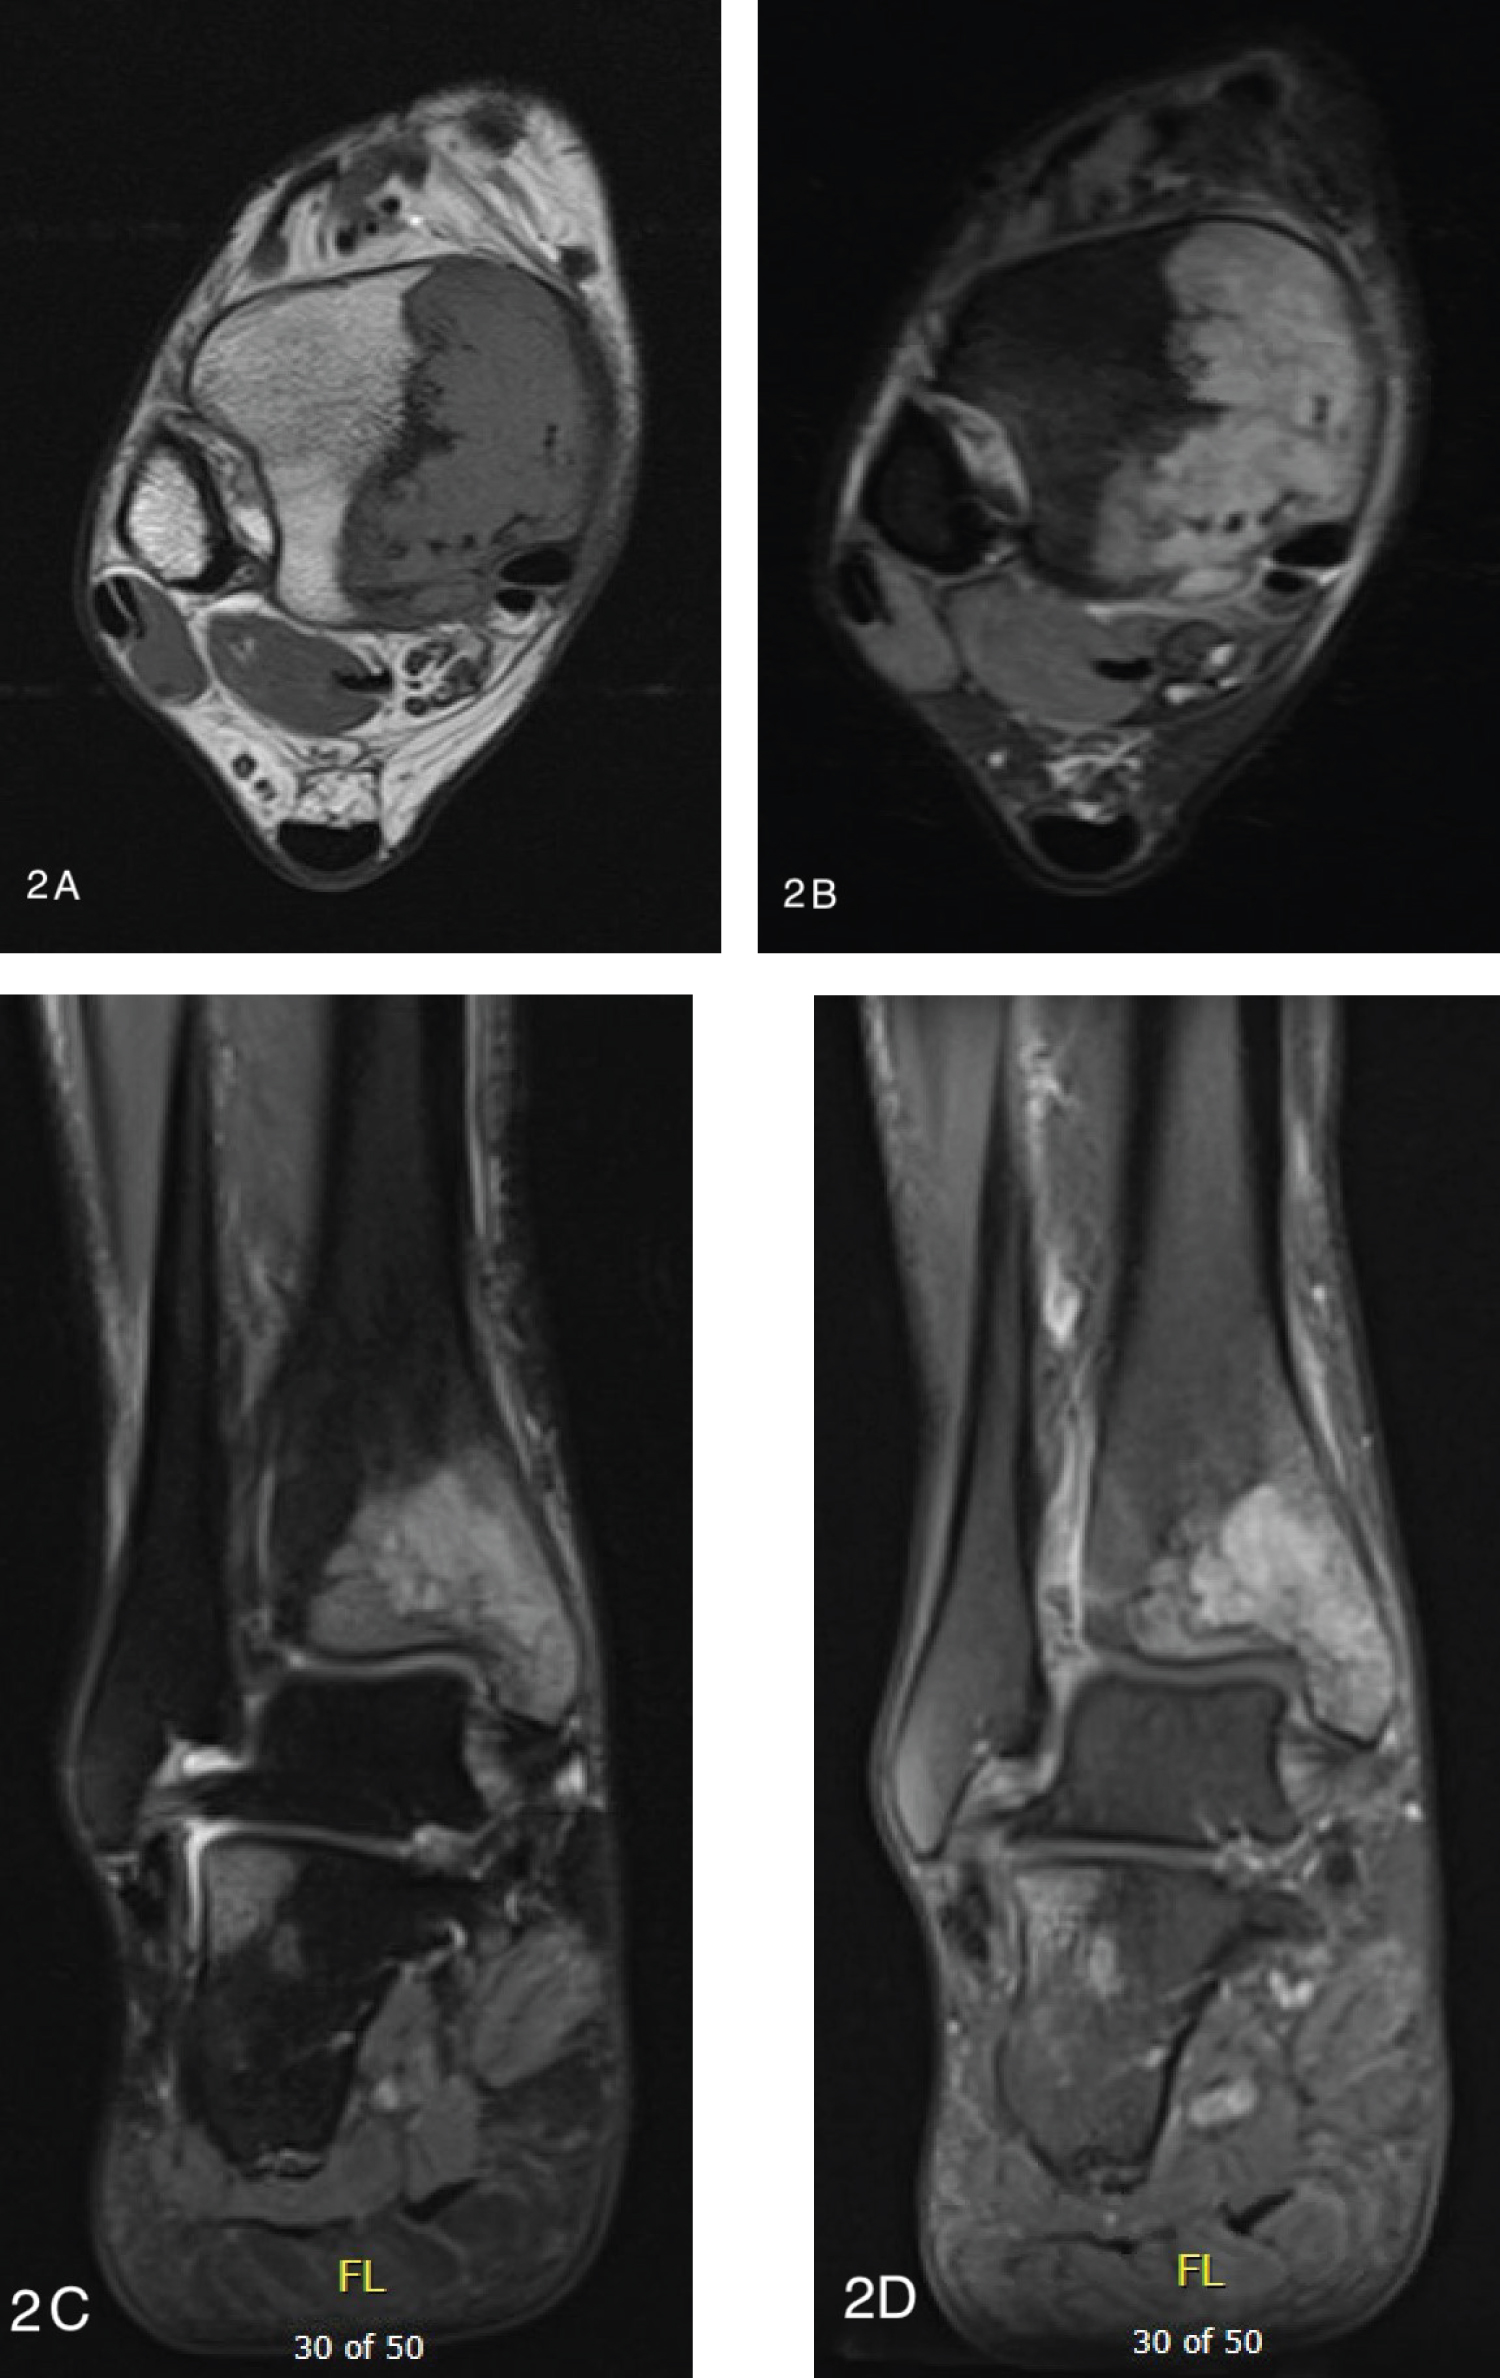

Conventional radiographs demonstrated a lytic bony lesion in the right medial malleolus (Figure 1). Magnetic resonance imaging (MRI) demonstrated a contrast enhancing marrow replacement lesion in the medial malleolus as well as the lateral calcaneus (Figure 2). Whole body bone scan demonstrated multiple lesions throughout the bilateral lower extremites (Figure 3).

Figure 1: Conventional radiographs of the ankle reveal a lytic lesion without substantial cortical involvement. AP (a) and lateral (b) images are shown. View Figure 1